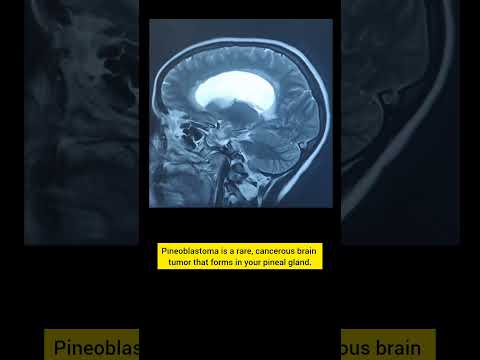

Hellow guys, Welcome to my website, and you are watching Lateral Supracerebellar Approach for Resection of a Pineoblastoma (Preview). and this vIdeo is uploaded by Neurosurgical Atlas by Aaron Cohen-Gadol, MD at 2014-02-11T08:20:01-08:00. We are pramote this video only for entertainment and educational perpose only. So, I hop you like our website.